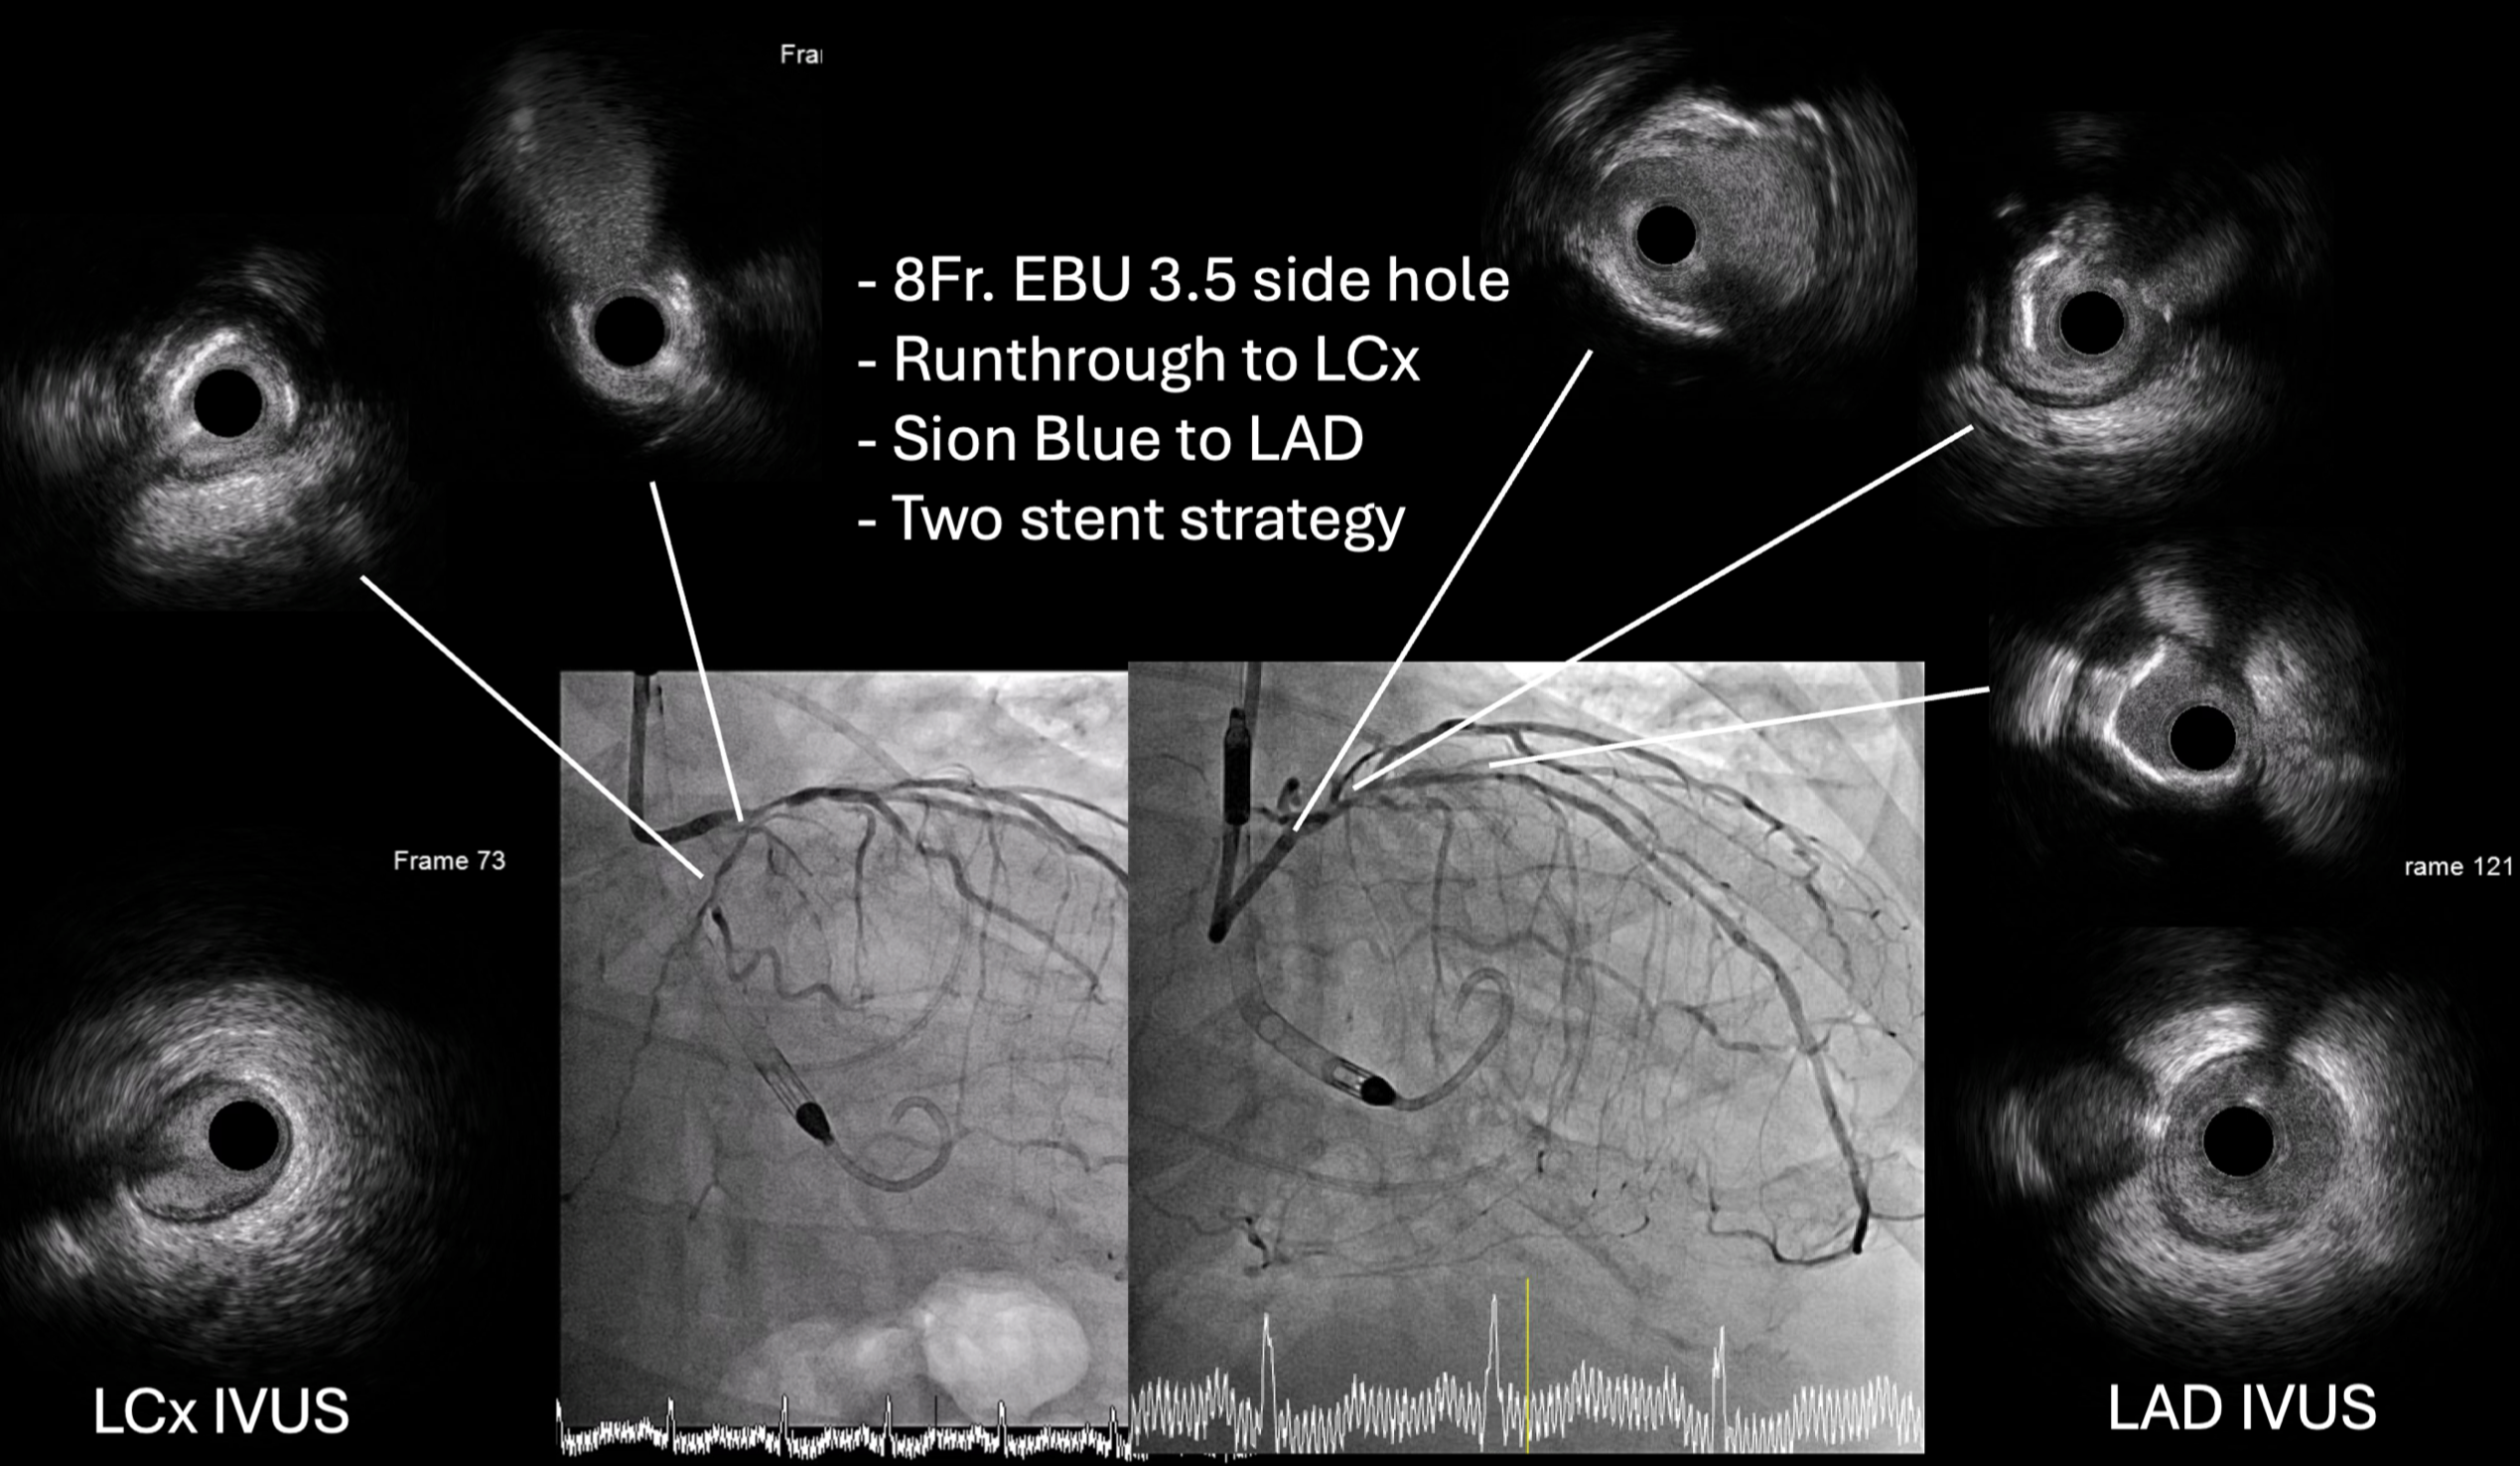

Vascular duplex was performed instead of CT for large-bore access evaluation due to acute kidney injury, revealing severe stenosis of the left common femoral artery. Despite this, an Impella CP¢ç sheath was successfully inserted using contralateral injection and fluoroscopic-guided puncture, and the device was advanced into the left ventricle uneventfully. Initial hemodynamic data from the pulmonary artery catheter showed elevated pulmonary artery wedge pressure (32 mmHg), pulmonary hypertension (68/22 mmHg, mean 43 mmHg), and a low cardiac index (1.98 L/min/m©÷) without vasopressors or inotropes. The wedge pressure decreased to 23 mmHg after Impella insertion, demonstrating effective hemodynamic support. A Medtronic 8 Fr EBU 3.5 guiding catheter with a side hole was used to engage the left coronary artery. IVUS of the LAD and LCx showed diffuse mixed calcified and fibrotic plaques with similar luminal diameters from the ostium to the proximal segments. Based on these findings, an upfront two-stent Culotte strategy was adopted. Both ostial-to-proximal LAD and LCx were pre-dilated with 3.0 mm balloons, followed by successful deployment of 3.0 ¡¿ 23 mm and 3.0 ¡¿ 28 mm drug-eluting stents to the LCx and LAD, respectively. The proximal-to-mid LAD and diagonal branch were also treated. After stent implantation, the patient was weaned smoothly from Impella, with pulmonary artery wedge pressure mildly elevated (23 mmHg after insertion and 25 mmHg post-procedure).